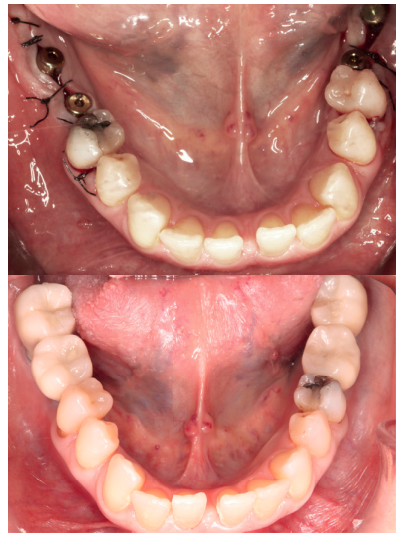

Caso clínico: Se presenta el caso clínico de una paciente con hipertensión, diabetes tipo II, hipotiroidismo, depresión, obesidad y déficit de vitamina D. Se hace una revisión de la actuación del odontólogo en la clínica cuando se presentan pacientes con dichos cuadros y las consideraciones a tener en cuenta con respecto a la prescripción y administración de medicación. El objetivo es presentar recomendaciones de tratamiento a partir de un caso clínico de una paciente con varias afecciones sistémicas en la que se realiza un tratamiento multidisciplinar. Para eso se ha realizado una revisión narrativa que se considera útil para la actividad clínica diaria

Clinical case: The clinical case of a patient with hypertension, type II diabetes, hypothyroidism, depression, obesity and vit D deficiency is presented. A review is made of the performance of the dentist in the clinic when patients with these conditions appear and the considerations to take into account with respect to the prescription and administration of medication. The objective is to present treatment recommendations based on a clinical case of a patient with several systemic conditions in which a multidisciplinary treatment is carried out. For this, a narrative review has been carried out that is considered useful for daily clinical activity.